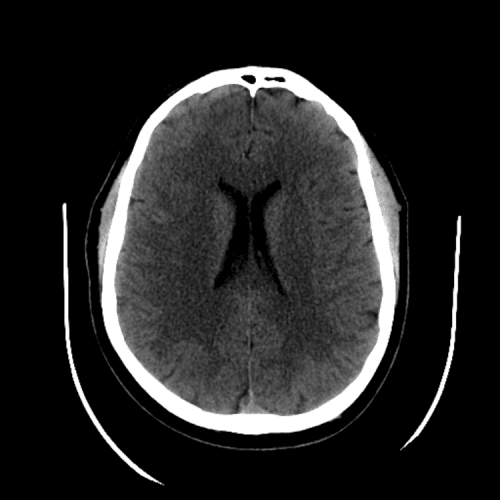

ACA and MCA territory infarct

Case #1